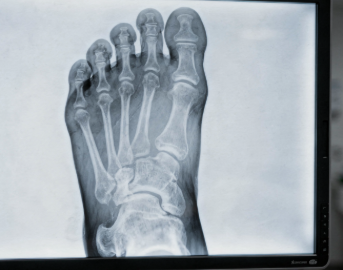

- 엑스레이(X-ray)

- 뼈돌기, 골절 여부 확인